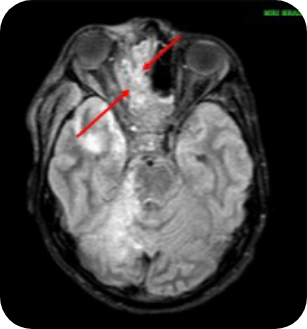

Evidence of stroke in Ahmad's right superior cerebellum and the

right side of his pons and mid‑brain, due to blockage of the right

superior cerebellar artery. He also had a blood clot in the right

cavernous sinuses. The scan showed signs of infection in his

right frontal, ethmoidal, sphenoidal and maxillary sinuses were also

visible alongside extensive inflammatory changes in Ahmad's right

masticator, carotid, pre-vertebral visceral spaces and

pre‑maxillary region.

Images supplied with permission of treating clinician.